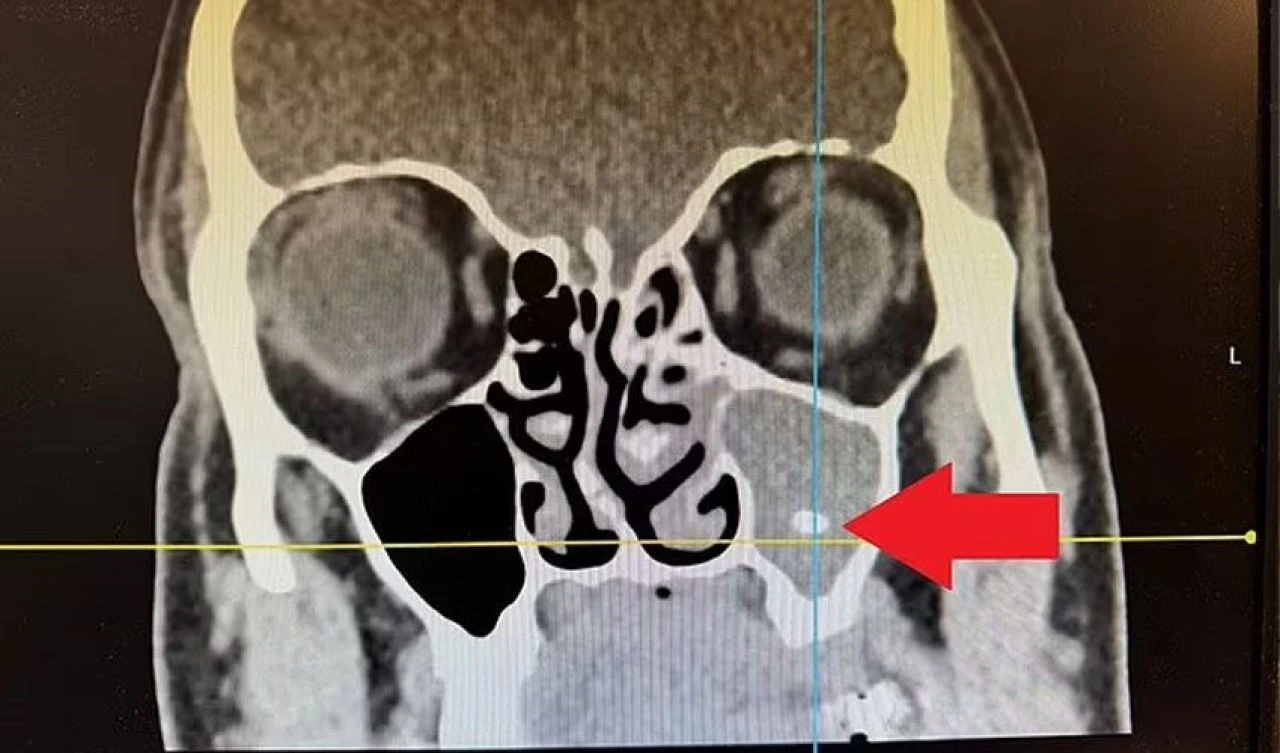

Mark Shire, kronik sinüzit hastasıydı ve tıkalı burnu nefes almayı zorlaştırıyordu. 58 yaşındaki Shire, bu duruma alışkın olsa da son zamanlarda yaşadığı baş ağrıları çok şiddetliydi ve gece nefes almakta zorlandığı için artık uyuyamamaya başladı. İki yıl süren acıların ardından doktora başvuran Shire'ın sinüslerinde bir diş kalıntısı fark edildi.

Mark Shire'ın sinüsünde bulunan diş parçası çıkarıldı ve kısa bir sürede sağlığına kavuştu.